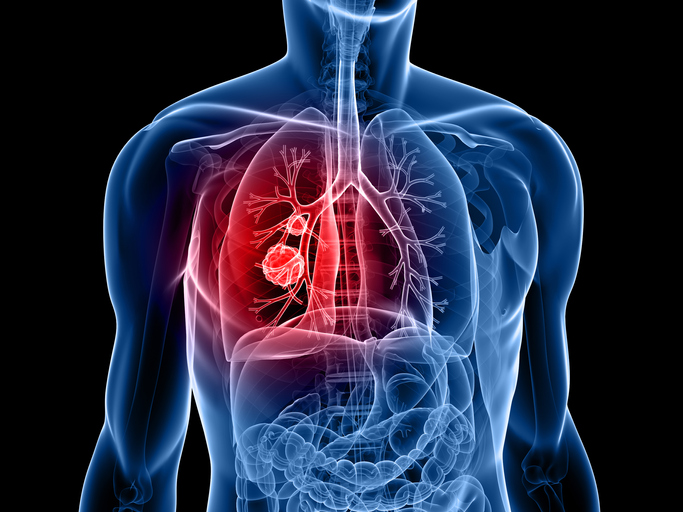

폐암은 원발성 폐암을 말하며 원발성 폐암은 폐에서 기원하는 악성 종양을 말한다. 폐로 전이된 암은 폐로 전이된 것으로 분류되며, 폐암이라기 보다는 기원 장기로 전이된 것으로 분류된다. 폐암은 조직학적 유형에 따라 크게 소세포폐암과 비소세포폐암으로 분류된다.

폐암의 초기증상 중에 흉통이 있습니다. 폐암 환자의 약 1/3이 흉통을 호소합니다. 흉통의 원인은 폐 가장자리에 종양이 형성되어 암세포를 생성하고 흉벽과 흉막에 침착되어 통증을 유발하는 것입니다.

흉통의 원인은 여러 가지가 있을 수 있지만, 오늘날 우리가 다루고 있는 폐암으로 인한 흉통은 경미한 통증보다는 지속적인 따끔거림과 둔한 통증을 동반한다는 점에 유의하시기 바랍니다. 또한 암은 흉막이나 흉벽 대신 갈비뼈로 퍼져 통증을 유발할 수 있습니다. 종양은 주변 조직 세포를 자극할 수 있으므로 계속해서 통증을 유발하는 경우 의사의 진찰을 받는 것이 좋습니다.